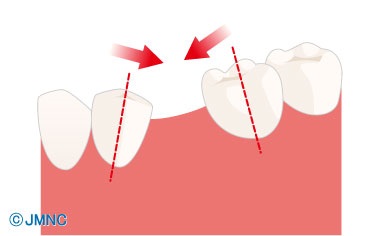

Mi történik a fogak, ha hosszú ideig nem visszaállítani törölt fogakat? Mozognak. És közben minden két szomszédos fogak elvesztek, és azokét, akik a szemközti állkapocs.

Ez a folyamat zajlik különböző mértékben különböző emberek, de az eredmény mindig ugyanaz - a képtelenség, hogy megfelelően visszaállítani a hiányzó fog, mert mert egyszerűen nincs hely maradt.

Minél több idő telik a foghúzás után megbukott protézis, annál nagyobb az eltolódás fogak. Sajnos keletkezik ebben fogazat deformációk vezethet új problémákat. A komplexitás a protézis a betegségek az állkapocsízület a jelentős malocclusions.

Például, az egyik változat szerint a törzs.